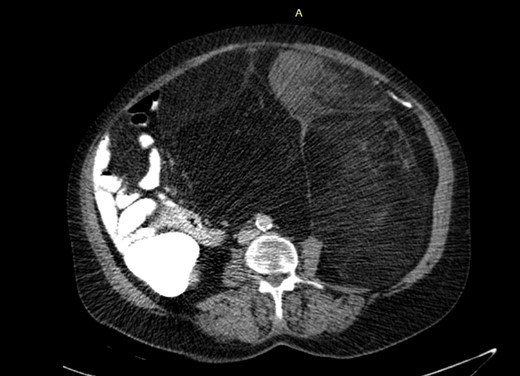

She had a free past medical, surgical and family history of malignancy or liver disease. Physical examination revealed a distended abdomen with a palpable mass about 3 cm below the xiphoid process, about 20 cm in diameter, which was hard and had limited mobility. The values of laboratory tests, including tumor markers (carcinoembryonic antigen, alpha-fetoprotein, cancer antigen 125, and cancer antigen 15-3) on admission were within the normal ranges. Abdominal computed tomography (CT) showed two large lobulated masses in both sides of the pelvis with dominant heterogeneous mass lesion in the right side measuring 15x10 cm with central fatty component causing displacement of vessels and bowel and another small left Para-aortic lesion measured 5x5cm (Fig. 1); Therefore, elective laparotomy with midline incision was approached with gross total resection of 35×22×17 cm retroperitoneal mass with smooth regular surface and without resection of any adjacent organs (Fig. 2A and B).

Abdominal CT: The mesenteric fat in the Abdominal cavity is bulky and heterogeneous with soft tissue component anteriorly.